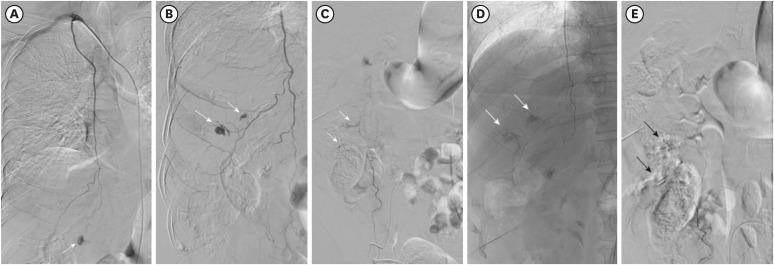

The use of neoadjuvant chemotherapy in older patients is increasing. However, chemotherapy should be administered considering the medical comorbidities of the patients and the toxicity of chemotherapeutic agents. Here, we present a case of abdominal wall hematoma with spontaneous inferior epigastric artery injury caused by coughing in a 70-year-old woman who was treated with neoadjuvant chemotherapy. Abdominal computed tomography demonstrated an abdominal wall hematoma with active bleeding. However, angiography with selective embolization of the right inferior epigastric artery and the right internal mammary artery was performed successfully. Scheduled chemotherapy was discontinued over concerns of rebleeding and breast-conserving surgery was performed. When deciding on chemotherapy for older patients, attention should be paid to the various complications.

老年患者新辅助化疗的应用正在增加。然而,化疗的实施应考虑患者的合并症以及化疗药物的毒性。在此,我们报告一例70岁接受新辅助化疗的女性患者,因咳嗽导致腹壁血肿伴自发性腹壁下动脉损伤。腹部计算机断层扫描显示腹壁血肿伴活动性出血。然而,成功地进行了选择性栓塞右腹壁下动脉和右乳内动脉的血管造影。出于再出血的担忧,预定的化疗被中止,并进行了保乳手术。在为老年患者决定化疗方案时,应注意各种并发症。